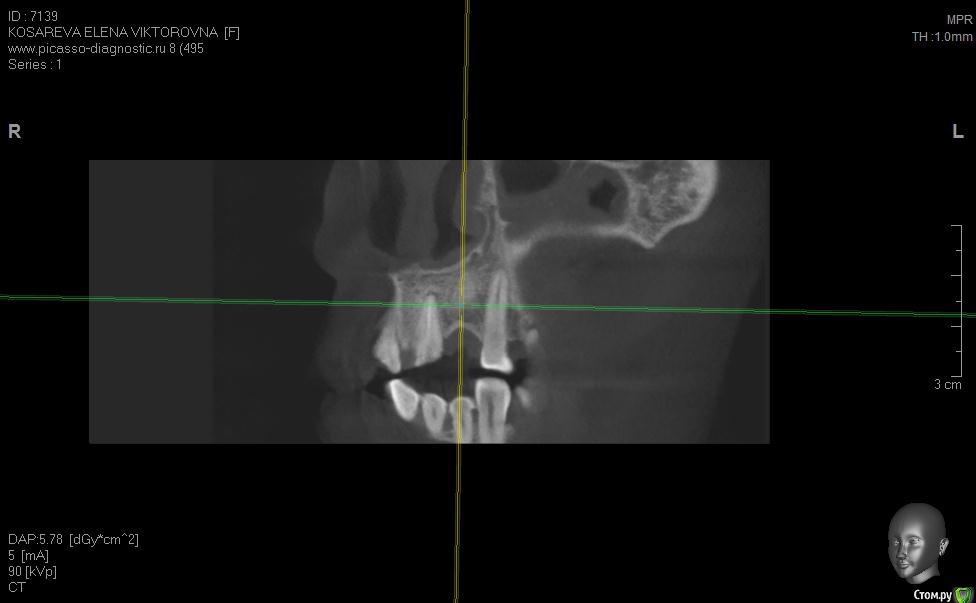

Уважаемые коллеги помогите пож с планом лечения, хотелось бы услышать ваши планы лечения,

пациент хочет красивую улыбку и импланты, клыки трогать категорически отказалась как опоры под временные на период интеграции имплантов